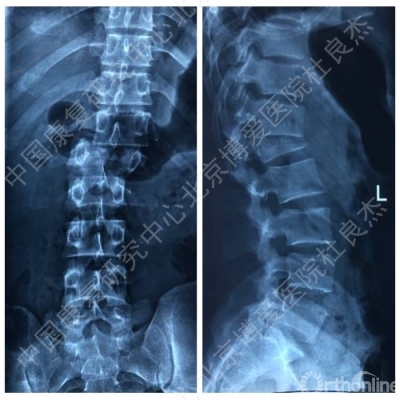

一月前干活时腰背部不慎被重约1吨重物砸伤,当时无意识障碍,无恶心、呕吐症状,自觉腰背部剧烈疼痛伴胸闷、憋气,双下肢失去知觉并不能活动,被送到当地医院救治,当时影像学检查示“腰1爆裂骨折伴脱位,腰1椎体附件骨折,腰2右侧横突骨折,胸12腰1之间侧方脱位,右侧第12肋椎关节脱位,右侧气胸,双肺挫伤,双侧胸腔积液”,经全面检查后诊断“胸12腰1骨折脱位,脊髓不全损伤,腰1椎体附件骨折,腰2右侧横突骨折,右侧第12肋椎关节脱位,右侧气胸,双肺挫伤,双侧胸腔积液等”。

手术前辅助检查

X线片

CT及三维重建

MRI图像